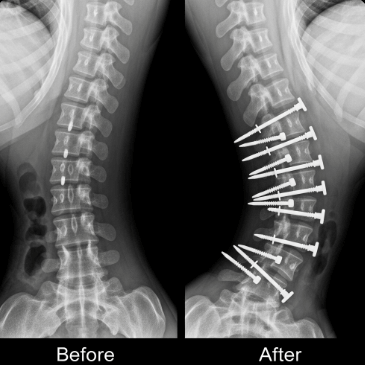

⚕️ 수술 치료 (45도 이상)

각도가 심하거나 계속 진행되는 경우 척추 유합술을 고려합니다. 금속 나사와 막대로 척추를 고정하는 수술이에요.

입원 기간은 보통 1~2주이며, 완전한 회복까지는 6개월~1년이 걸립니다.